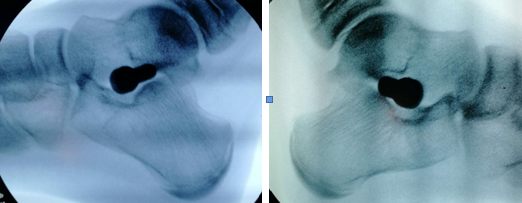

术中照片

扁平足的微创手术是通过小切口,放置一个稳定器(螺钉),将足弓撑起来,随着儿童年龄的增长,骨骼进行塑形改造,重建儿童足弓。该手术操作简单、创伤小、并发症少、疗效较为确切满意。

小馨馨的手术切口大约1.5cm,术后一周下床行走。